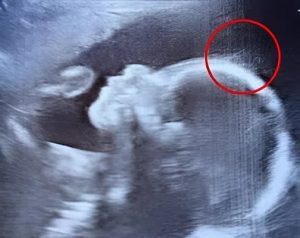

Doctors couldn’t believe what

When 29-year-old Emily Foster from Kent, England, walked into the hospital for her 20-week pregnancy scan, she expected the usual routine: a grainy image, a few measurements,…